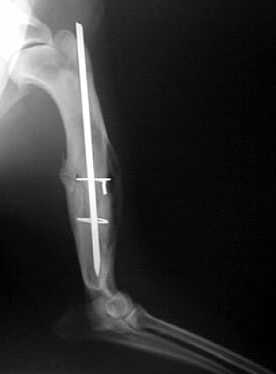

Oberarm-Trümmerfraktur

Marknagelung